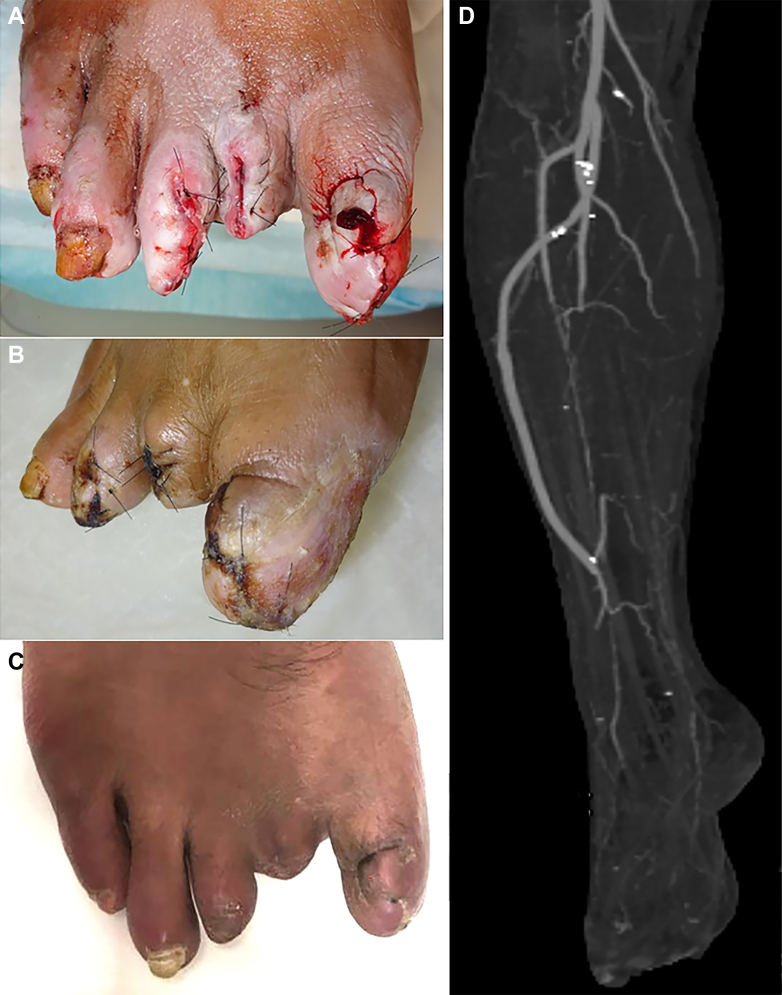

A 38-year-old man had been admitted to our hospital because of intractable gangrene on his right toes that had persisted for 2 months. He was a heavy smoker and obese (body mass index, 27.8 kg/m2), with a medical history of hypertension and diabetes mellitus. His renal function was normal, and he had no history of ischemic heart disease or cerebrovascular disease. The physical examination revealed pulselessness of the right dorsal and posterior tibial arteries and infected necrosis of digits one through three on the right foot (Fig 1, A). His right ankle brachial index was 0.83, and his skin perfusion pressure (SPP) was 21 mm Hg on the plantar surface and 23 mm Hg on the dorsum. The limb was categorized as WIfI (wound, ischemia, foot infection) clinical stage 4 (wound grade 2, ischemia grade 3, foot infection grade 2).3

Fig 1.

Photograph of the patient’s right foot and radiographic findings before revascularization. A, The first to third digits of his right foot were infected with gangrene at admission. B, Enhanced computed tomography (CT) of the right lower limb, with CT angiography showing that the iliac, femoral, and popliteal arteries were not diseased. The infrapopliteal arteries were occluded from the proximal third of the right lower leg to the ankle, except for the distal third of the peroneal artery (PA; white arrow). C, Axial CT scan of the right leg showing the relationship between the PA (white arrow) and leg bones. D,E, Digital subtraction angiography of the lower limb showing severely diseased infrapopliteal and dorsalis pedis arteries with poor outflow, except for the distal segment of the PA (white arrow), which had remained partially patent through the collateral vessels.

Postoperative photographs and computed tomography angiography findings of the right foot. A, Wounds after minor amputation and surgical revascularization. B, Photograph showing wounds at 10 days after revascularization. C, Photograph showing complete wound healing at 2 months after revascularization. D, Postoperative computed tomography angiogram showing good patency of the vein graft.